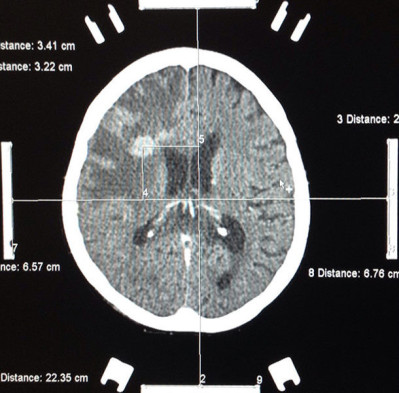

Casos Neuroloquirúrgicos

Envíado por Dr. Ruben Eduardo Amaya Contreras